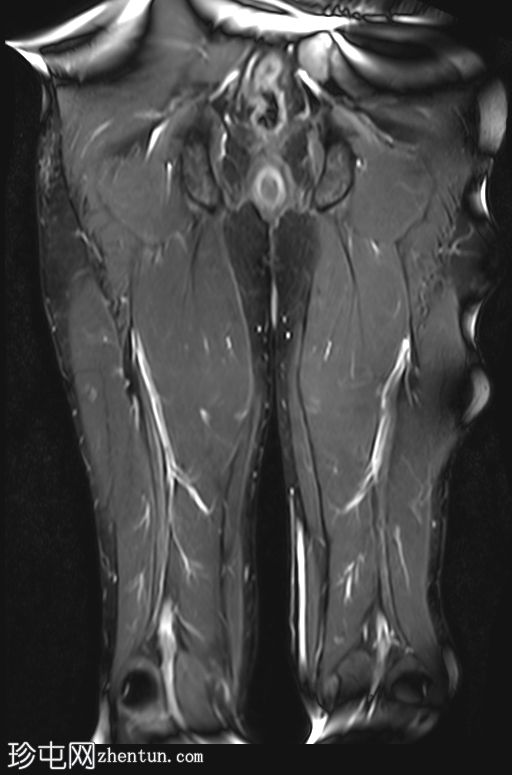

冠状位

T1加权像

影像显示右侧阔筋膜张肌(TFL)拉伤,伴有水肿,阔筋膜浅层受累。

右侧缝匠肌也可见轻度拉伤,肌间液在股直肌、缝匠肌和阔筋膜张肌之间流动。

此外,筋膜水肿沿髂胫束向下延伸,髂胫束是一条从髂嵴延伸至胫骨外侧的厚筋膜带。

未见局灶性纤维断裂或肉眼可见的撕裂。未见血肿。